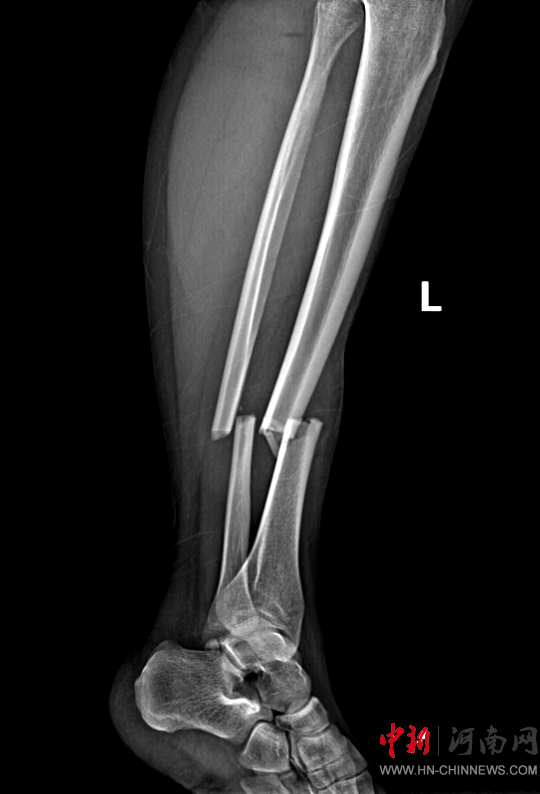

患者,女,32歲,車禍傷,到達(dá)確山縣人民醫(yī)院急診科創(chuàng)傷中心救治時(shí)血壓80/45mmHg,心率115次/分,處于昏迷、休克狀態(tài),病情危重。急診科迅速啟動(dòng)創(chuàng)傷中心急救綠色通道,醫(yī)護(hù)人員立即展開搶救,積極抗休克治療的同時(shí),聯(lián)系神經(jīng)外科、胸外科、急診重癥監(jiān)護(hù)室緊急會診,同時(shí)快速CT、床旁FAST檢查明確診斷。通過一系列急救措施,患者的休克狀態(tài)稍微好轉(zhuǎn),經(jīng)多學(xué)科會診后明確診斷為:多處損傷并失血性休克、彌漫性軸索損傷、蛛網(wǎng)膜下腔出血、腦挫傷、股骨及脛腓骨粉碎性骨折、多發(fā)肋骨骨折并肺挫傷、腰椎骨折。ISS評分高達(dá)50分,死亡率極高,患者病情危重,立即送入急診重癥監(jiān)護(hù)室進(jìn)行高級生命支持治療。

患者病情好轉(zhuǎn)后,該院急診科主任岳春彥和創(chuàng)傷治療團(tuán)隊(duì)為患者制定了詳細(xì)的手術(shù)規(guī)劃,傷后第10日,患者在全身麻醉下進(jìn)行“左股骨粉碎骨折及脛骨粉碎骨折髓內(nèi)釘內(nèi)固定術(shù)+骨移植術(shù)、腓骨骨折復(fù)位內(nèi)固定術(shù)”,病情平穩(wěn)后轉(zhuǎn)入急診科病房治療,切口愈合后,患者轉(zhuǎn)入康復(fù)醫(yī)學(xué)科進(jìn)行腦功能康復(fù)和下肢關(guān)節(jié)康復(fù)治療。目前,患者能夠與人正常溝通交流,左下肢關(guān)節(jié)功能也恢復(fù)良好,已出院。